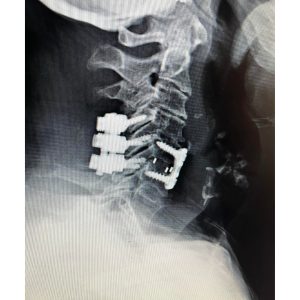

The first 2 pictures are a CT scan and then an MRI of the C5-6 fracture with spinal cord compression. The next is X-ray taken during surgery. The last is X-ray at 2 months postoperative. At 2 months after surgery, the patient is living at home again. She is as strong as ever!”